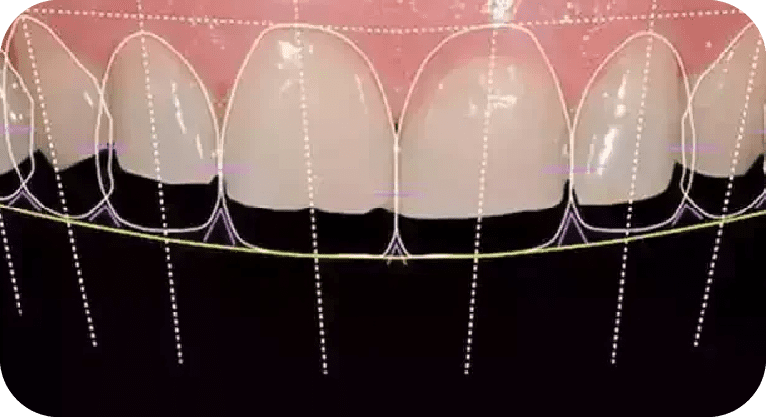

Male patient, “33” years old

Treatment: Smile design

The patient was dissatisfied with the aesthetics of his front teeth. Aer clinical diagnosis and digital analysis, a smile design with porcelain veneers was performed to correct tooth shape, position, and size, achieving a harmonious and natural appearance that met his aesthetic expectations.